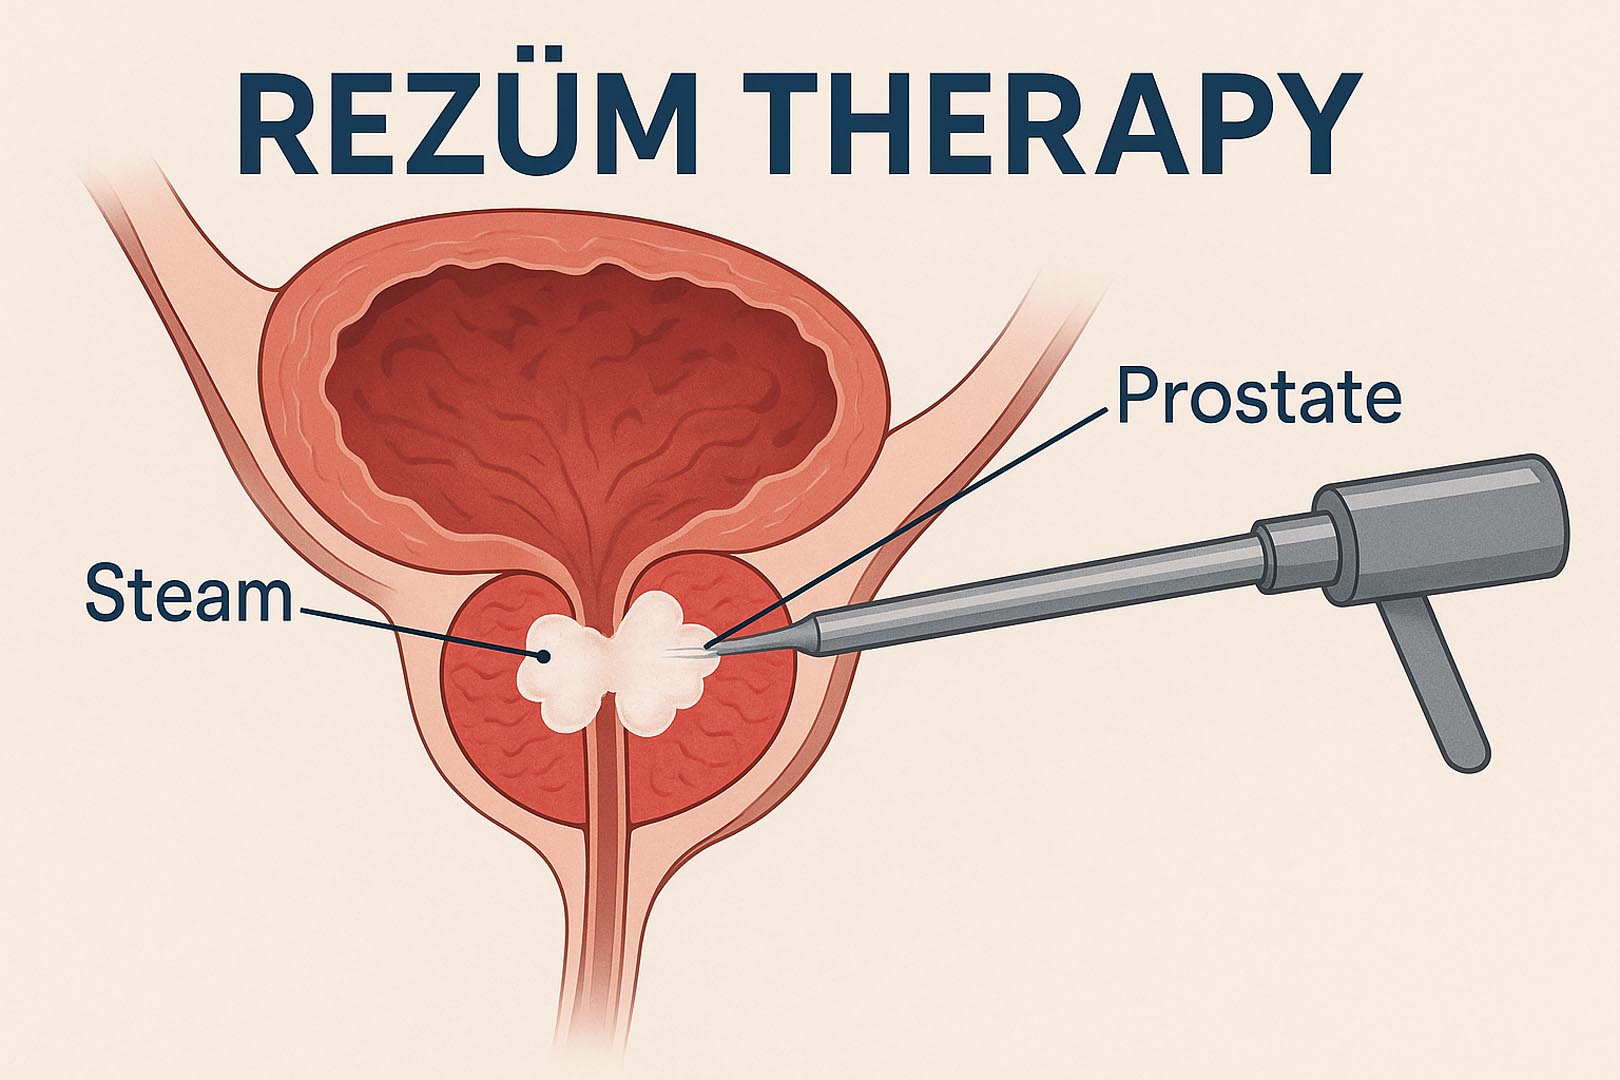

Rezum™ Therapy - Vapore Acqueo Termico

Tecnologia a vapore che riduce selettivamente il volume della prostata. Trattamento ambulatoriale in pochi minuti, nessuna incisione, recupero rapido. Mantiene intatta la funzione sessuale.